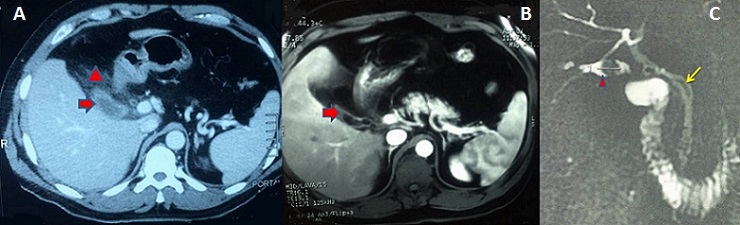

Une cholécystectomie subtotale expose au risque de cholécystite sur moignon, bien qu'elle constitue une option sûre face à une inflammation sévère du triangle de Calot permettant de réduire le risque de plaie biliaire. Malgré une histoire parfois typique, le diagnostic est souvent retardé en raison d'une faible suspicion. Par conséquent les cliniciens devraient évoquer ce diagnostic. Une fois le diagnostic confirmé, il convient de réaliser une ré-intervention pour exciser le moignon. Nous rapportons le cas d'un patient agé de 43 ans opéré par laparotomie sous-costale droite pour un pyo-cholécyste lithiasique. Il a été réalisé une cholécystectomie. L'examen anatomo-pathologique avait conclu à une cholécystite aiguë avec péri-cholécystite. Deux ans après, le patient présentait un syndrome douloureux et fébrile de l'hypocondre droit depuis trois jours et a été traité à tort pour pneumopathie droite avec une radiographie thoracique normale. A l'examen, le patient était fébrile à 38,5°c, et il existait une défense à la palpation de l'hypocondre droit. Il existait un syndrome inflammatoire biologique. L'échographie était non contributive. La tomodensitométrie (A) avait montré un aspect d'une cholécystite sur moignon avec une infiltration importante tout autour. L'IRM abdominale (B,C) avait montré une néo-cavité au niveau du lit vésiculaire d'environ 3,5x1,5 cm contenant une concrétion lithiasique ovalaire de 15 mm de grand axe qui se continue avec le canal cystique sans dilatation des voies biliaires. Sous couverture antibiotique, la reprise de la sous-costale avait permis, difficilement, l'exérèse du moignon et une cholangiographie per-opératoire montrant une vacuité des voies biliaires. Les suites opératoires étaient simples.